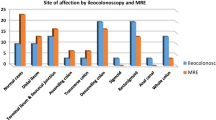

In recent years, the accuracy of MRI for the detection of ileocolonic IBD has been investigated by means of MRI colonography. After administration of rectal contrast medium the colon (and sometimes the terminal ileum) was assessed for disease. Conflicting results were reported: while in one study high accuracy values were reported [59], in others segmental sensitivity values were around 32% [60, 61].

Regarding the accuracy of MRI in differentiation between CD and UC conflicting results have been reported; while some authors report that based on the location of inflammatory changes, the degree of involvement, the continuity or discontinuity of disease, and the presence of complications it was possible to differentiate between CD and UC [51, 62], others report a limited value in differentiation of disease [63].